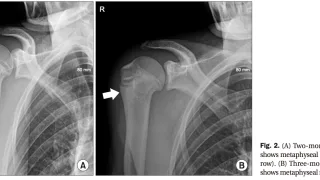

手術日+779日目 2026/4/17(金)(小児上腕骨外顆骨折)

午前の病院での仕事今朝は, 快晴.しかし, 気温は低めで, クルマの外気温モニターでは9 ℃.寒く感じました.8時前に病棟に上がり, 8時から朝の病棟回診.8時半から, カンファランス.今日は, 外科医師によるフレイルと栄養障害についての講...